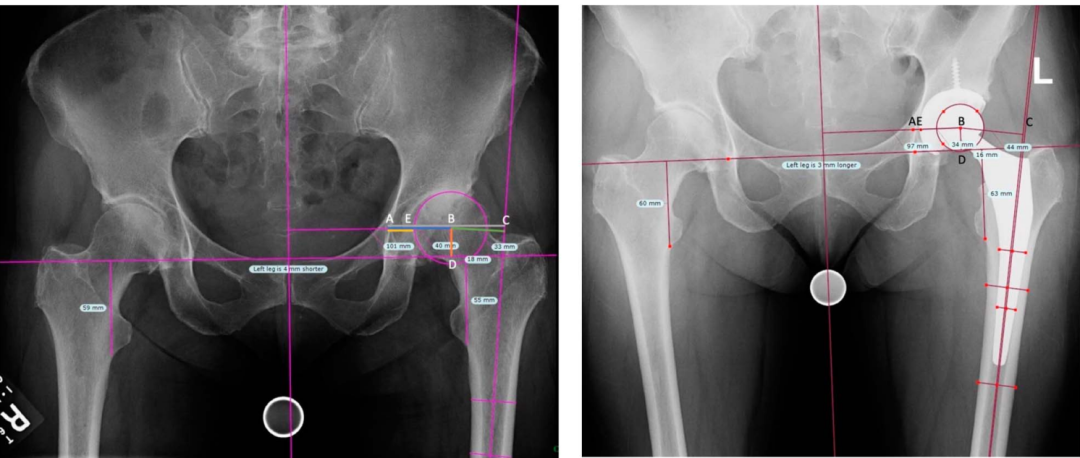

对2007年至2013年间接受THA的患者进行回顾性分析。在术前和术后的X线片上测量髋臼偏距(Acetabular Offset,AO)。髋臼偏距的变化量定义为术后测量值减去术前测量值。

共纳入149例患者,其中117例患者接受了长期(至少10年)随访且无需翻修手术,31例患者因髋臼杯无菌性松动在THA后平均7.7年需接受翻修手术。髋臼偏距无变化或增加(对应髋关节中心无变化或外移)的患者,其无菌性松动的发生几率是髋臼偏距减小(对应髋关节中心内移)患者的2.9倍(95%置信区间为1.3至6.6;P = 0.0097)。因无菌性松动接受翻修手术的患者,其髋臼偏距的变化量显著大于未接受翻修手术的患者,前者比后者多2.6毫米(翻修组增加0.7毫米,非翻修组减少1.9毫米;P = 0.013)。同样,在控制糖尿病和体重指数因素后进行多元回归分析显示,髋臼偏距平均变化量存在2.6毫米的差异(P = 0.018)。